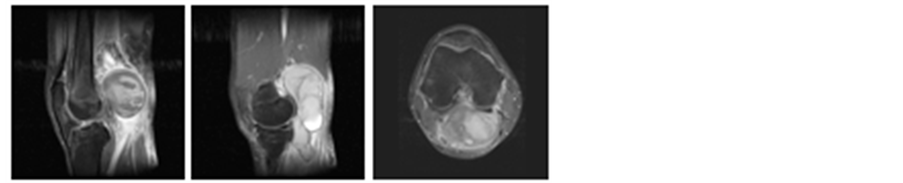

Synovial osteochondromatosis is a disorder of the synovial lining characterized by cartilage hyperplasia and synovial neoplasia resulting in the formation of cartilaginous nodules or chondromas. Most of these eventually calcify to become osteochondromas and a small percentage will undergo ossification. Nodules are released into the joint space forming loose bodies, which can cause mechanical joint pain, joint locking, and joint effusions. Synovial osteochondromatosis has an incidence of 1 in 10,000, is mono-articular in 95% of cases and 50% of cases involve the knee. On MRI, three appearances have been described: type A, which contain non-mineralized lesions; type B, which contain mineralized lesions; and type C, which contain adipose tissue [10] . The non-mi- neralized (chondroma) type is found in 16% of cases and displays low/intermediate intensity on T1 and high signal intensity on T2 and may be difficult to distinguish from synovial fluid or mass. In this case, contrast can be helpful as these lesions typically show rim enhancement as they have a vascular supply from the synovium [11] . The mineralized type accounts for 75% of cases and is of low signal intensity on T1 and T2 sequences, Figure 4. Nodules in type C are isointense to fat and show high signal on T1 and intermediate signal on T2.

Figure 4. Synovial Osteochondromatosis in a patient following knee arthroplasty. Note the low T1 and T2 mineralized foci within the lesion (a) T1 sagittal; (b) T2 Axial sequences.